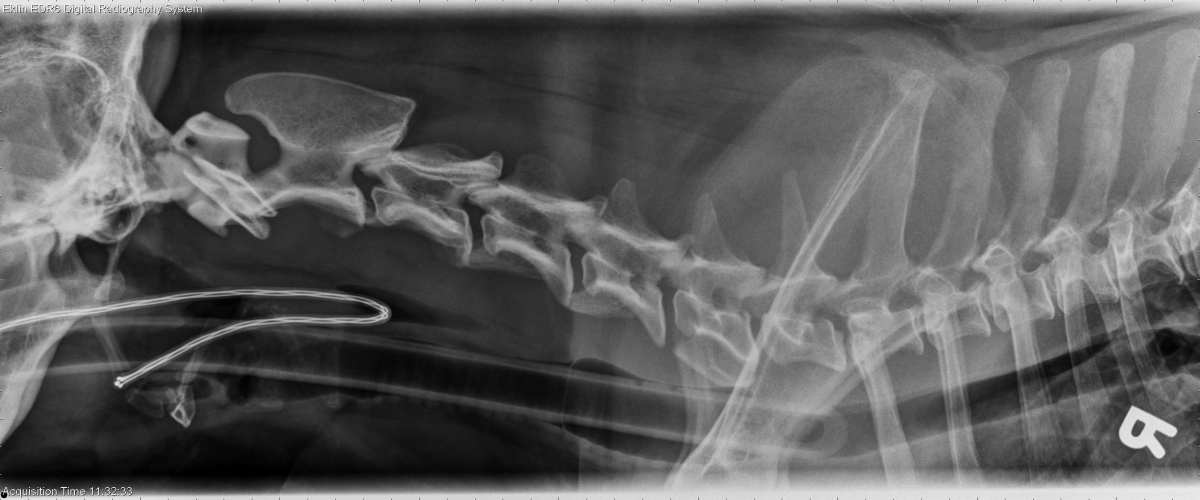

R LAT Spine

There are multiple sites of spondylosis deformans including T9-10, T13-L1, and the lumbosacral junction. There is sclerosis and irregularity of multiple caudal thoracic and lumbar vertebral articular facets. There is sclerosis and an irregular cranial and caudal contour of the dorsal spinous process of T4. There is beginning lysis of the T2, T3 & T5 dorsal spinous processes.

Lysis of spinous processes from T2 -T5; soft tissue neoplasia with secondary bone lysis is a primary consideration.

Soft tissue sarcoma invading the dorsal spinous processes bilaterally and spinal canal on the left side at T4.